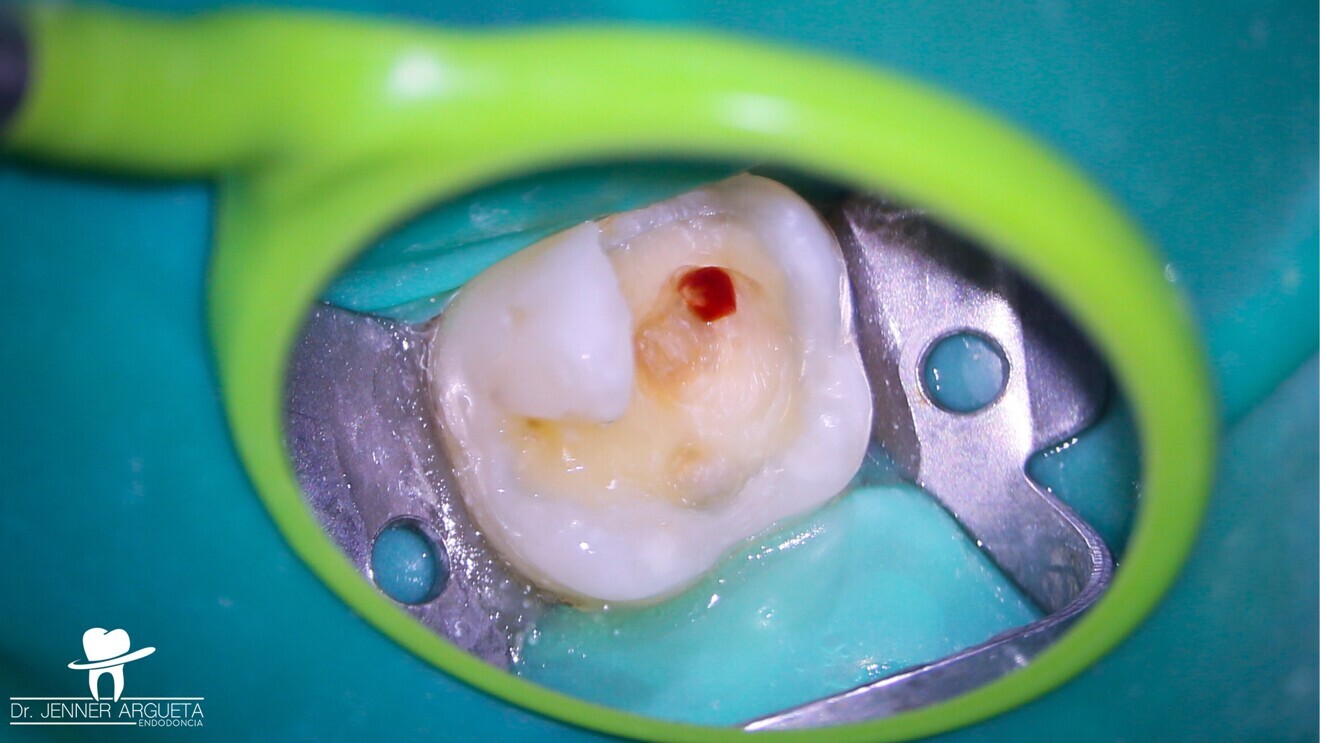

Fig. 1: Tooth #16 with temporary restoration. Total isolation prior to the removal of caries. (All images: Dr Jenner Argueta Endodoncia)

In the clinical case presented in this article, we describe the recommended technique for performing direct pulp capping in cases of frank pulp exposure with a diagnosis of reversible pulpitis. This clinical scenario was selected because it is the one that occurs most frequently.

The patient attended reporting short-term pain in tooth #16 (Fig. 1). Through radiography, clinical assessment and an analysis of the patient’s clinical history, reversible pulpitis was diagnosed, and a deep Class II temporary restoration was found (Fig. 2).